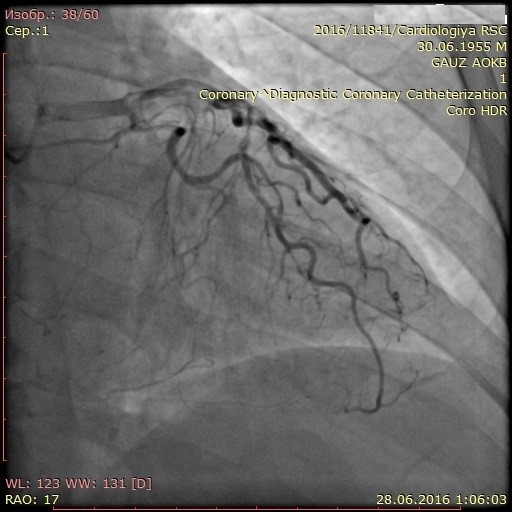

Материал и методы: 90 пациентов с трехсосудистым поражением коронарного русла и обязательным наличием окклюзии правой коронарной артерии (ПКА) в зависимости от варианта развития коллатерального крвоснабжения были разделены на две группы: в первую группу вошли 44 пациента (44%) с наличем коллатералей I и II степени градации по Rentrop, во вторую группу – 46 пациентов (56%) с наличием коллатералей 3 градации по Rentrop. Проанализированы данные перфузионной сцинтиграфии, эхокардиографии и тканевой допплерографии.

Результаты: Выявлено ухудшение перфузии миокарда по нижней стенке у пациента из второй группы при незначимом дефекте перфузии у пациента из первой группы. СДП в 1 группе составил 9,8±3,5%, во второй группе – 4,1±1,7%. При сравнении показателей тканевой допплерографии более значимое изменение продольной деформации в области нижней стенки левого желудочка выявлено в группе с плохим коллатеральным руслом: – 4,1±2,6, во 2 группе: – 6,8±2,7. При оценке сегментарной сократимости нижней стенки левого желудочка выявлено меньшее количество сегментов гипокинеза в группе 2.

Заключение: Хроническая окклюзия коронарной артерии со слабым коллатеральным кровоснабжением сопровождается худшими показателями локальных перфузии и функции миокарда. При хорошем развитии коллатералей, несмотря на незначимые нарушения перфузии миокарда в покое, имеются отчетливые стресс-дефекты перфузии и нарушения локальной сократимости миокарда.